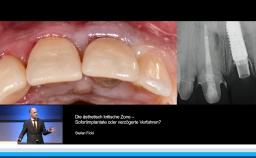

Diese Präsentation zeigt anhand von Patientenfällen verschiedene Gründe für die Erneuerung von vorhandenem implantatgetragenem Zahnersatz auf. Neben Fehlern bei der Abutmentwahl und der Planung und den veränderten funktionellen und ästhetischen Ansprüchen der Patienten/-innen, spielt natürlich auch der Funktionsverlust eine große Rolle. Auch auf modulierende Faktoren wie das Alter der Versorgungen, Alter der Patienten/-innen, Hygienefähigkeit und Patientenwünsche wird eingegangen. Die prothetische Backward-Planung in ihren funktionellen Dimensionen wird dargestellt und für die Neuversorgungen werden konventionelle analoge Produktionsverfahren den modernen digitalen Möglichkeiten gegenübergestellt.